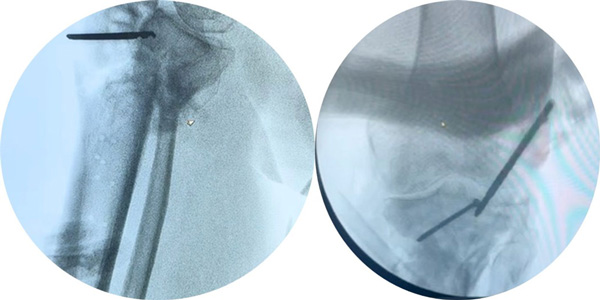

Intra-operative pictures